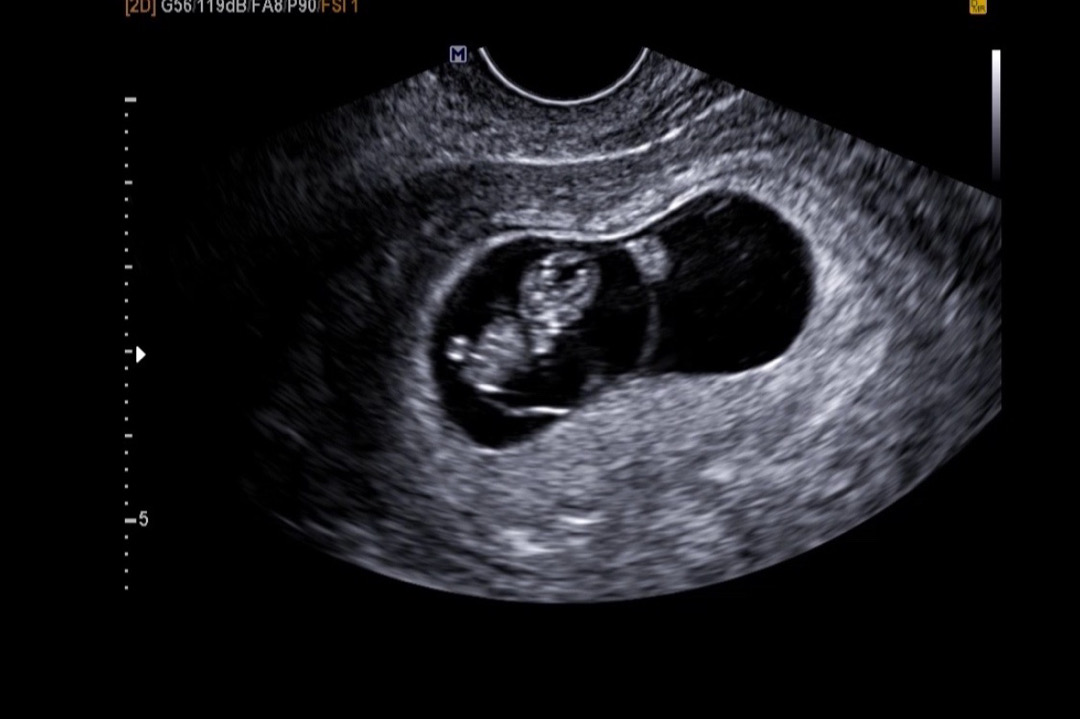

8주6일차 젤리곰🧸

9주차 되기 직전 초음파 사진을 받아봤는데 ㅎㅎ인간의 형태로 진화해서 너무 신기해요!! 눈팅만 하다 처음 글쓰기 해봅니당>< 저는 아직 입덧을 하나도 안하는데 언제쯤 할까요?